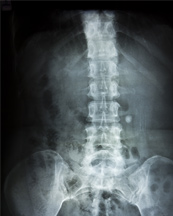

A corpectomy is a spinal surgery procedure in which a portion of a vertebra and adjacent intervertebral discs are removed to allow decompression of the spinal nerves. It may be performed in the neck, or cervical region of the spine, a procedure called a cervical corpectomy, or in the lower, or lumbar region, called a lumbar corpectomy. Spine fusion surgery is often performed following the corpectomy, incorporating a bone graft and in many cases a metal plate attached by screws to adjacent vertebrae, to provide stability to the spine, as the corpectomy compromises the strength of the involved vertebra.

Vertebral discs naturally degenerate with age, and the loss of cushioning and attendant wear on the vertebrae, as well as thickening of spinal ligaments, can lead to the formation of bone spurs. These changes can narrow the spinal canal and press on the spinal nerves, causing radiating pain, numbness, and muscle weakness. In such cases a discectomy alone – the surgical removal of an intervertebral disc – cannot decompress the spinal cord and nerve roots sufficiently to relieve pain or restore mobility caused by degeneration of the discs. The surgery may also be recommended in cases where spinal tumors are impinging on spinal nerves, or in cases of traumatic spinal injury.

In the corpectomy procedure the affected vertebral body is removed, and the space is reconstructed, often with titanium, plastic (PEEK), or carbon fiber cages, and bone is grafted to promote fusion between adjacent vertebrae. As noted, the vertebra is often further stabilized by securing it to adjacent vertebrae with screws secured by rods. A plate with screws may be placed upon the area of the vertebral body where bone was removed to facilitate the fusion process. Here at New Jersey Spine Specialists, we have performed corpectomies on patients from throughout the region and beyond, and we believe it is an excellent treatment option for some patients with severe compression of spinal nerves caused by degenerative disc disease, trauma, tumor or other medical conditions.